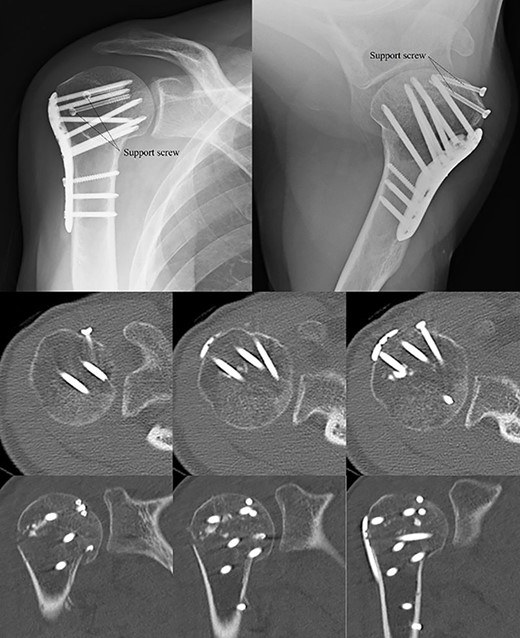

Postoperative radiographic and CT evaluations showed reduced fractures on the humeral head and surgical neck (Fig. 7). At 24 months of postoperative follow-up, radiographic and CT evaluations showed no signs of osteoarthritis or reimpression (Fig. 8). Two years after the primary surgery, we performed implant removal at the patient’s request (Fig. 9). When performing implant removal, we additionally performed a second-look evaluation with arthroscopy to assess the degree of healing in the joint. We noted no impression or exposure of cartilage callus on either side of the humeral head or glenoid (Fig. 10).

Postoperative X-ray and CT scan showing sustained anatomical reconstruction of articular surfaces and no signs of osteoarthritis.